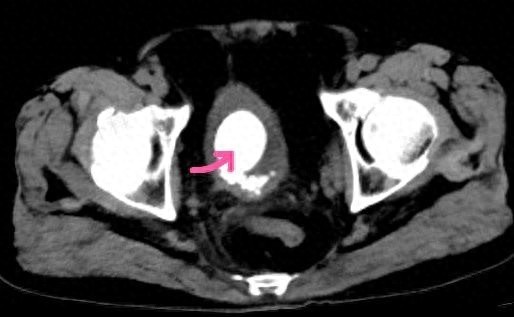

检查结果让大家都吃了一惊:吴老前列腺增生严重,体积超过正常人的4倍;膀胱里长满了结石,最大的直径达5厘米,足足有鸡蛋大小;同时合并泌尿道感染。

接诊的泌尿外科副主任医师钱晓辉解释,吴老长期患有前列腺增生,压迫尿道导致排尿不畅,膀胱不得不“加倍用力”收缩,时间一长,膀胱壁就变得粗糙不平,加上他平时喝水少、又爱吃豆制品,尿液中的结晶逐渐沉积,最终形成了这20多颗大小不一的结石。

为解决患者痛苦,泌尿外科主任郭涛主任医师团队为吴老进行了微创手术,先用钬激光将膀胱里的结石逐一击碎取出,再行前列腺剜除术解除尿道梗阻。术后,吴老的排尿痛苦明显缓解,血尿消失,恢复良好。